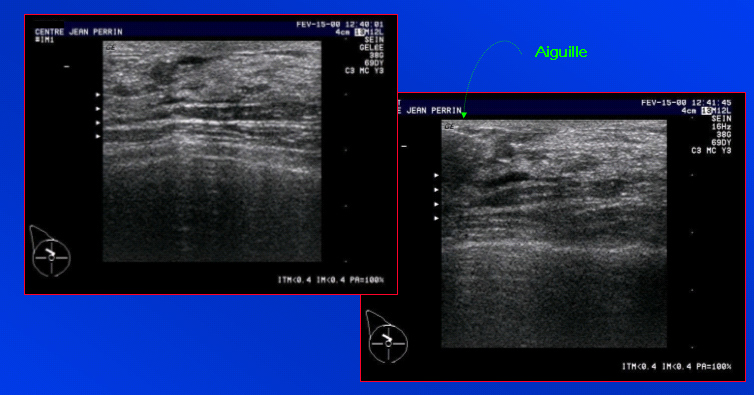

Petite lacune très superficielle, abord indirect ; il s’agit d’un petit kyste | Iconographie précédente | Retour cours | Index iconographique | Iconographie suivante |